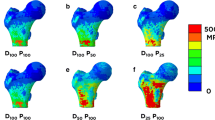

Virtual lowering of tube currents and sparse sampling using FBP (Fig. 2a) and SIR (Fig. 2b) were successfully achieved in all enrolled subjects. The effective dose of the original scans was estimated to range between 3.6 and 9.1 mSv with a scanning length of 30 cm. BMD measurements for full-dose data using FBP, considered as the current clinical standard, were 0.849 ± 0.106 g/cm3 (range 0.640–1.060 g/cm3) in the femoral neck (Table 1).

Low-dose and sparse-sampled multi-detector computed tomography (MDCT). This figure shows axial slices of the femoral neck derived from full-dose MDCT (D100 P100) as well as MDCT at 50% (D50), 25% (D25), and 10% (D10) of the original tube current applied (100% tube current = D100). Furthermore, sparse sampling was performed to achieve 50% (P50), 25% (P25), and 10% (P10) of the original projection data (100% projections = P100). For all settings presented in this figure, filtered back projection (FBP; a) and statistical iterative reconstruction (SIR; b) were used for image reconstructions

FBP- and SIR-based BMD values showed an increase with a virtual lowering of the tube current up to 1.125 ± 0.175 g/cm3 for FBP (D10 P100) and 1.130 ± 0.175 g/cm3 for SIR (D10 P100), respectively (Table 1 and Fig. 3a, b). Thus, the values for virtual lowering of tube currents showed relative changes up to 32.5% (FBP) and 32.3% (SIR).

Regarding sparse-sampled data, BMD measurements remained comparatively stable in the course of reductions in the number of projections, which was true for both MDCT with FBP and SIR (Table 1 and Fig. 3a, b). Hence, the changes of BMD values regarding sparse-sampled data were clinically acceptable, with small relative changes of up to 0.5% (FBP) and 0.7% (SIR), respectively.